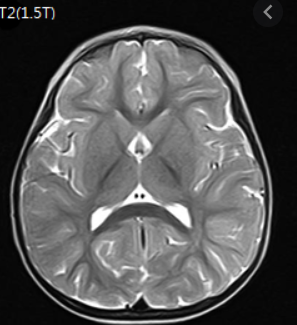

2018년 10월에 뇌 MRI 보험적용이 바뀌게 됩니다. 2018년 10월 이전에는 중증 뇌질환환자로 의사가 인정하는 경우에만 제한적으로 건강보험 적용이 되었습니다. 해당 상병으로는 뇌출혈, 외전증, 뇌경색 등이 있습니다.

하지만 2018년 10월에는 뇌혈관 및 뇌 MRI 가 건강보험 적용이 확대 되었습니다. 경증인 뇌질환이나 신경학적으로 이상이 있거나, 검사상 이상소견이 있다면 건강보험이 적용이 가능해졌습니다.

그리고 뇌질환이 의심되는 두통이 있거나, 어지러움이 있고 신경학적 검사를 실시한 경우에도 건강보험이 적용이 되어서 많은 국민들의 부담이 줄어들었습니다.